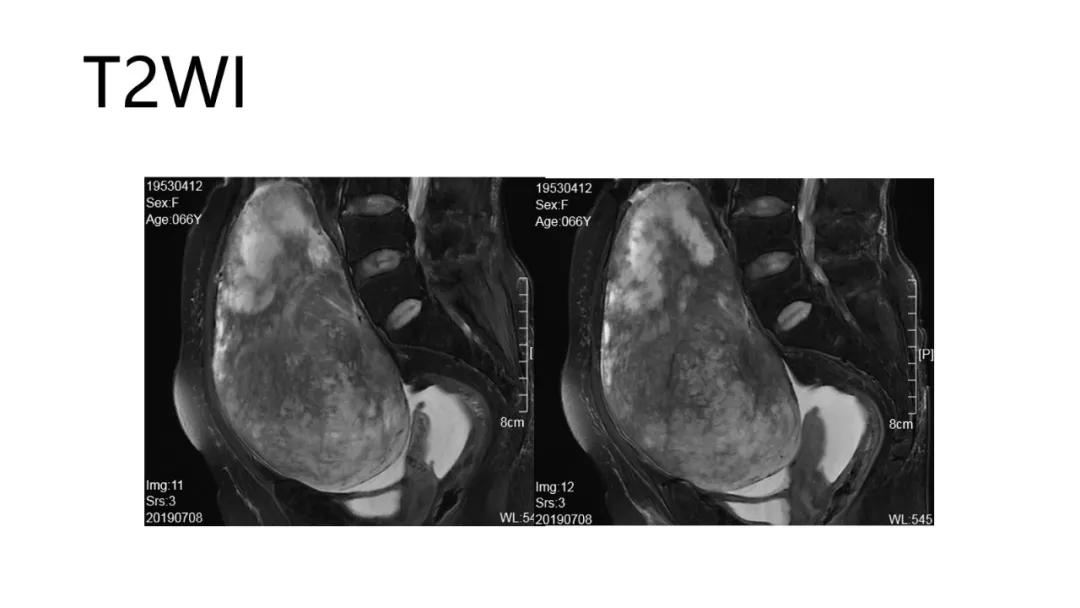

病理:颗粒细胞瘤

病理:子宫肌瘤粘液样变性